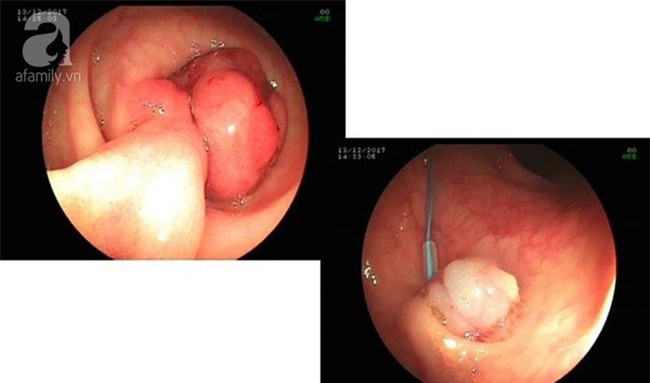

Cắt polyp đại tràng qua nội soi.

Đó là nội soi nhuộm màu, nội soi phóng đại, siêu âm qua nội soi và đặc biệt là kỹ thuật ESD (cắt tách dưới niêm qua nội soi) để cắt khối u trong dạ dày.

"ESD là phương pháp điều trị ung thư dạ dày sớm và tổn thương tiền ung thư, được tiến hành hành qua nội soi thực quản dạ dày với thuốc tiền mê hoặc gây mê.

Đây là một kỹ thuật cao có rất nhiều lợi ích, nhưng ở Việt Nam phần lớn ung thư dạ dày được phát hiện ở giai đoạn muộn nên không thể áp dụng điều trị cho người bệnh được.

Vì vậy, việc nội soi và phát hiện sớm căn bệnh này là rất quan trọng" - BS Kinoshita Koshi, bệnh viện Trung ương Kyoto Min-iren chia sẻ.